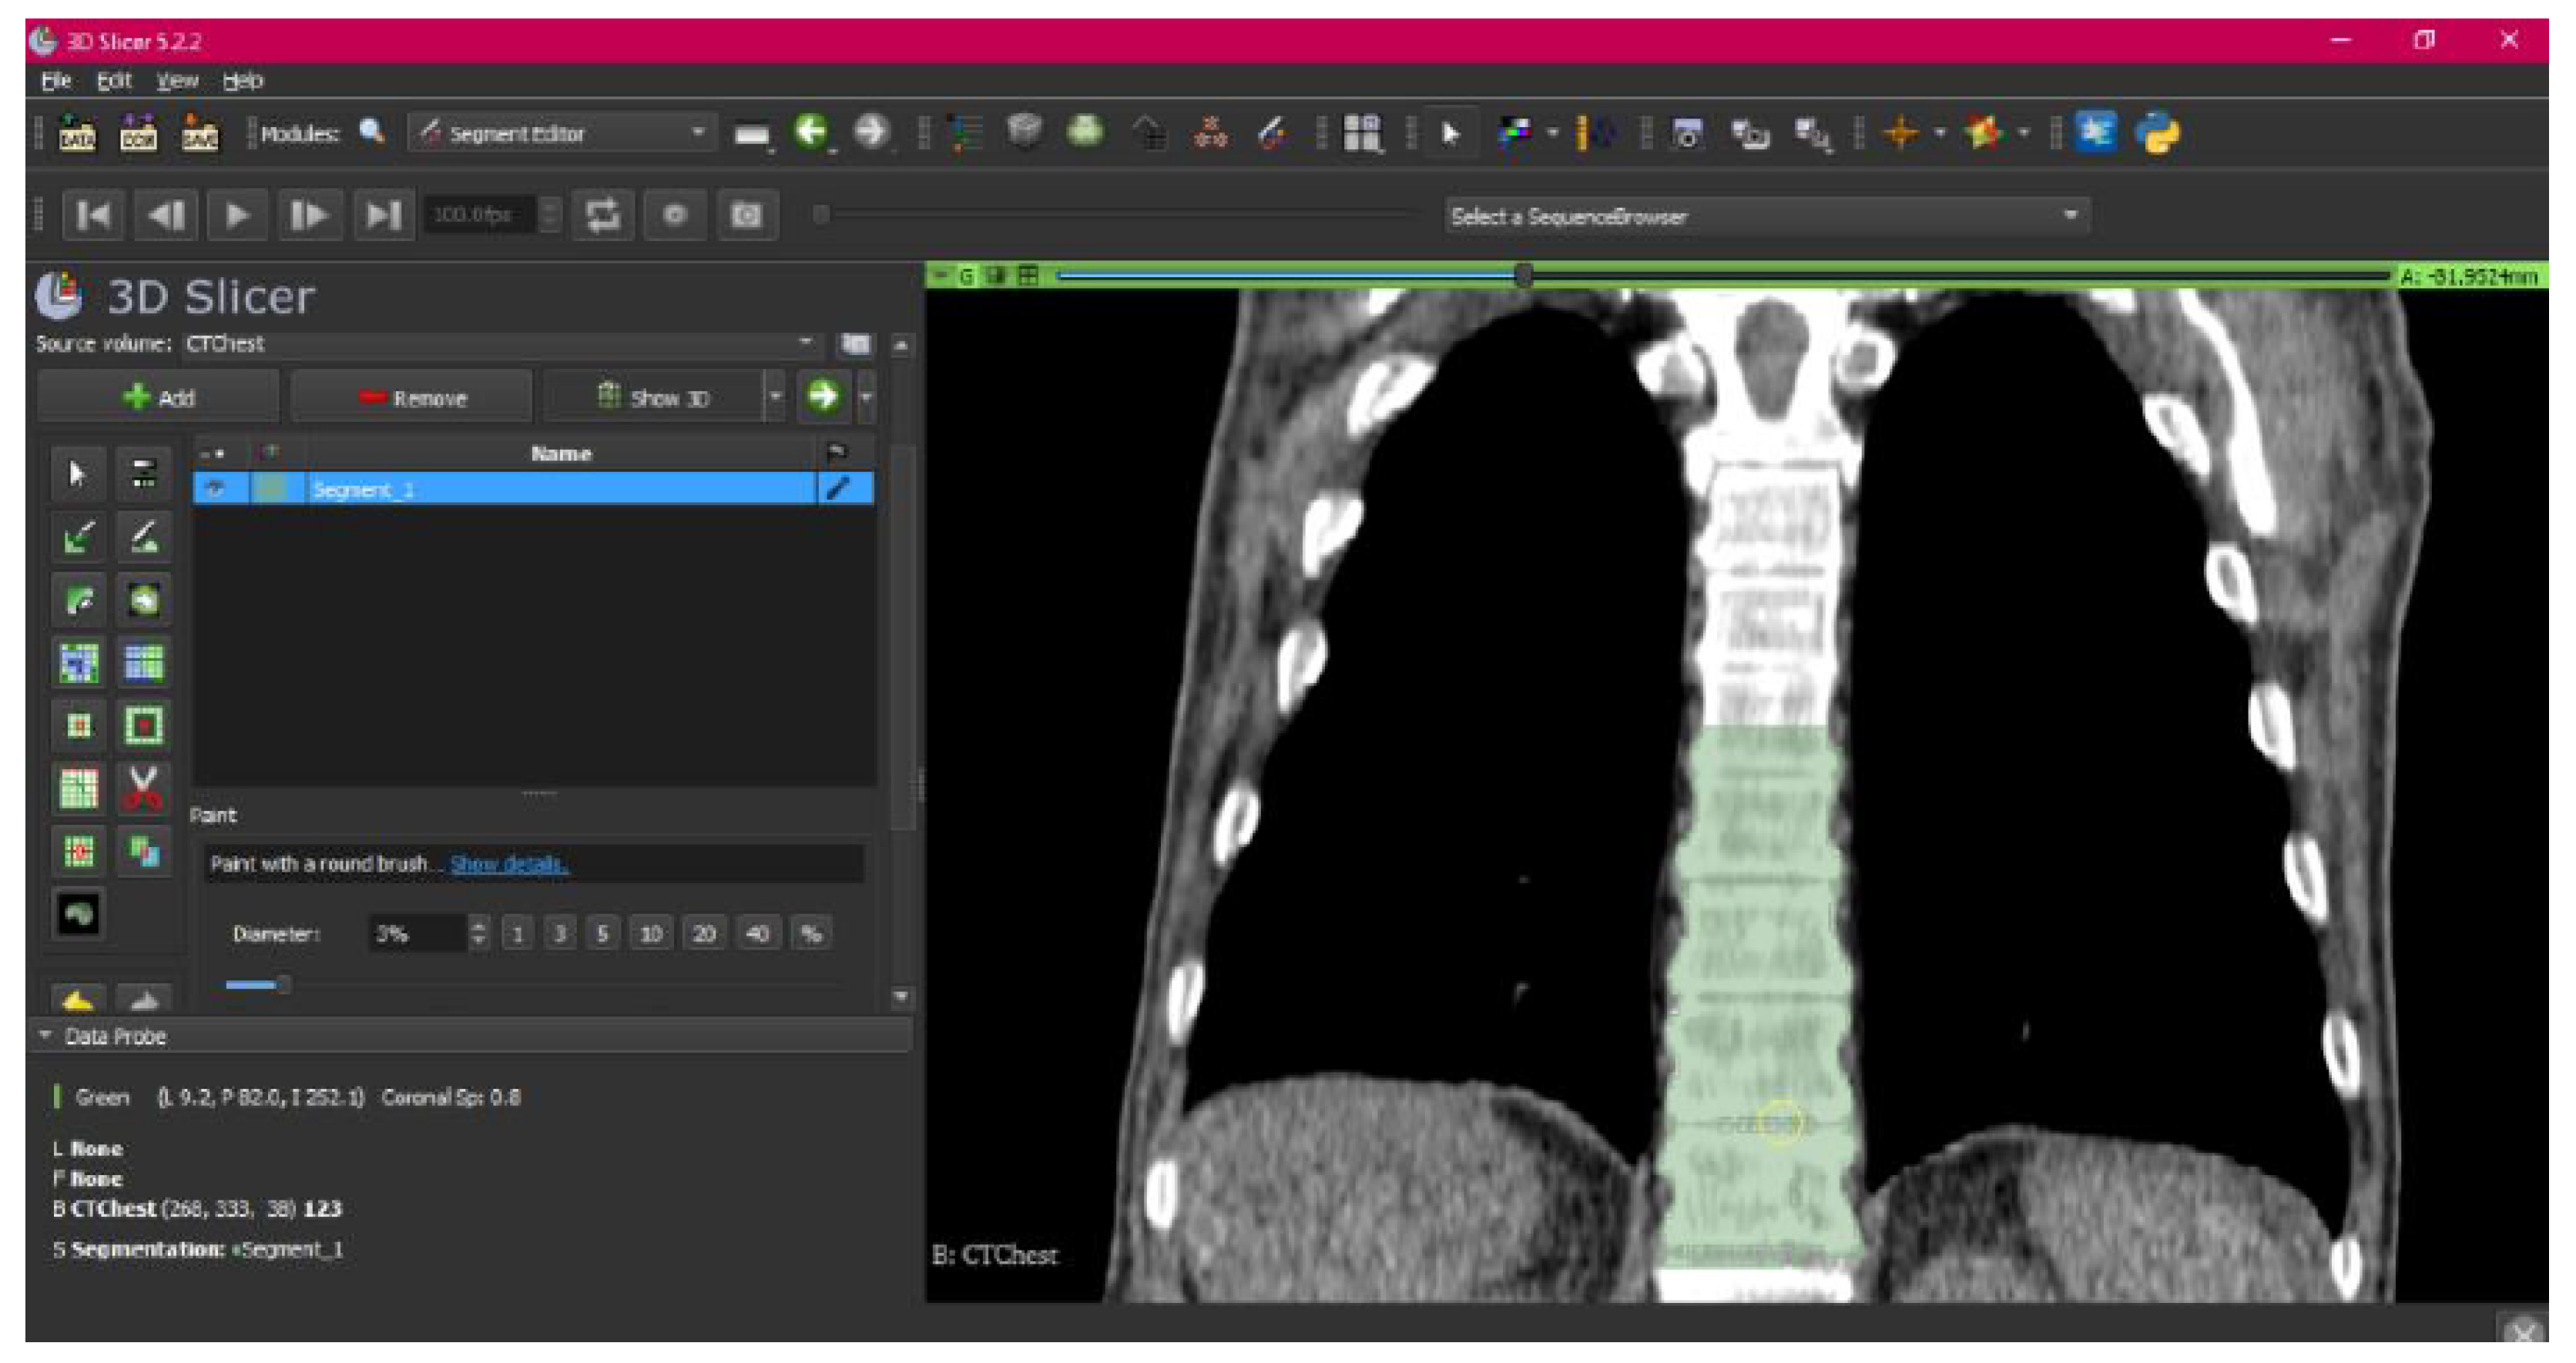

- Use the “Paint” tool.

- Paint those parts which have not been selected yet and which form part of the model for each one of the “cuts” of the three views.